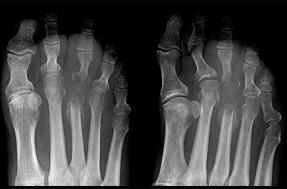

女,55岁,第3趾肿胀,结合图像,最可能的诊断是 ( )A、结核B、化脓毒性关节炎并骨髓炎C、未见异常D、骨髓炎E、化脓性关节炎

问题 女,55岁,第3趾肿胀,结合图像,最可能的诊断是 ( )

选项 A、结核 B、化脓毒性关节炎并骨髓炎 C、未见异常 D、骨髓炎 E、化脓性关节炎

答案 B